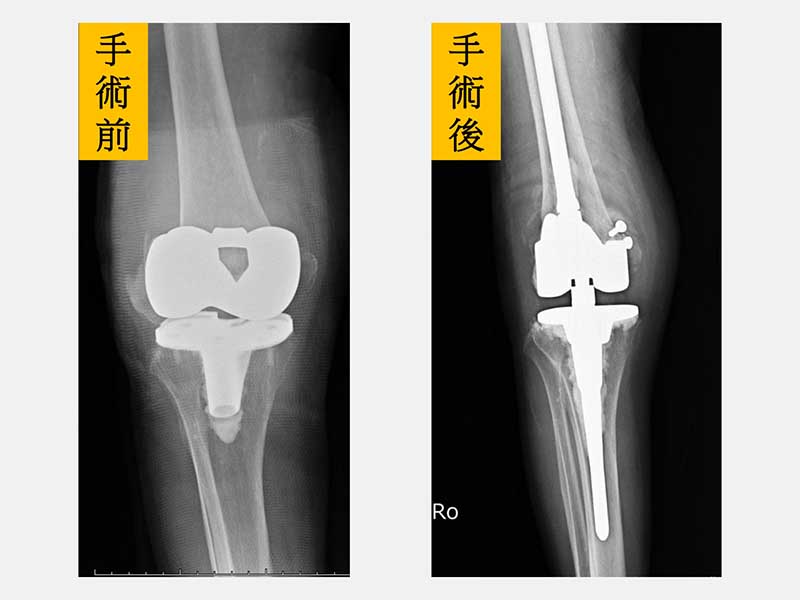

黃贊文部長指出,根據健保署的資料顯示,2024年台灣民眾接受人工關節置換手術高達3萬7千人次。隨著台灣在2025年進入超高齡社會,罹患退化性關節炎的民眾將越來越多。不僅需要接受人工關節置換手術的年齡層越來越高,像黃老太太一樣因為骨質疏鬆症而導致人工關節旁骨折的老人家也越來越多。黃部長回憶門診當天的情形,老太太一臉沮喪由家屬推著輪椅來到門診,X光一看是人工膝關節旁的粉碎性骨折,由於年紀大骨質疏鬆嚴重,人工關節就像地基出現天坑一樣也整個鬆動。當天剛好是她的生日,痛苦了一個星期,生日願望只希望在餘生還能再站起來走路。

由於老太太的骨質疏鬆嚴重,不僅是粉碎性骨折也連帶傷到膝關節的韌帶。黃部長使用新式預鎖式樞紐設計的人工關節,可以取代韌帶的功能也可填充骨頭缺損來重建一個穩定的膝關節。老太太手術當天下午就可以自己拿著助行器下床上廁所。此外,從手術隔天開始,除了骨質疏鬆症的治療,還搭配手術後疼痛中醫輔助醫療,復健科醫師也根據老太太的需求安排復健運動,在病床邊開始固定式腳踏車訓練。在手術後第5天,老太太開心的出院走路回家。